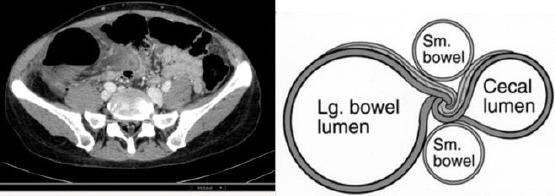

Caecum volvulus (CV) is defined as an axial twisting that causes an inversion position of the caecum, ascending colon and terminal ileum. This anatomical finding is responsible for some clinical features. Obstruction and strangulation are the most important and life-threatening.

盲肠扭转(CV)被定义为一种导致盲肠、升结肠和回肠末端发生倒转位置的轴向扭转。这一解剖学发现导致了一些临床特征。梗阻和绞窄是最重要且危及生命的。